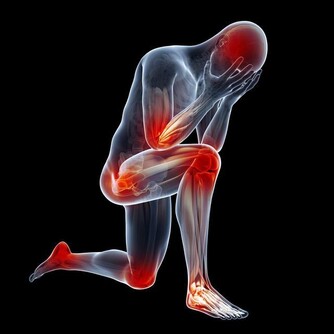

手麻與腳麻主要表現為局部刺痛、麻木或感覺異常,這可能是由於神經受到壓迫、血液循環不良或其他健康問題所引起。根據最新的健康研究,這些症狀不僅僅是短暫的不適,也可能是身體發出的緊訊,提醒我們及時關注潛在的疾病風險。

除了上述原因,一些慢性疾病也可能引起手麻與腳麻的症狀:

- 自體免疫性疾病:如多發性硬化症或類風濕性關節炎,這些疾病可能攻擊神經系統,導致麻木感。